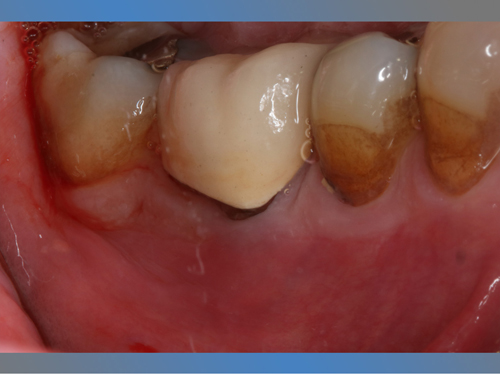

Nuestro paciente Eduardo Vicente Pedrós ha tenido en varias ocasiones infecciones en dientes que estaban desvitalizado. Él nos explica perfectamente en el vídeo que la cirugía periapical (o apicectomía) es un tratamiento que permite salvar la mayoría de los dientes afectados de esta patología.

Los implantes son una buena herramienta, pero sin duda lo mejor son los propios dientes naturales. Con la cirugía periapical nuestros pacientes tienen la oportunidad de conservar sus propios dientes afectados de infección en el hueso periapical.